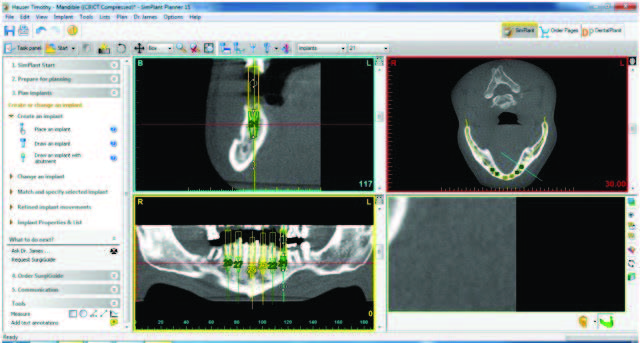

After evaluation of their finances and budget, a treatment was reverse engineered to provide them with a solution. While this patient was communicative and able to carry on a conversation, the issues related to patient care in the post-treatment phase had to be engineered into the prosthetic design. Records were taken, including photographs, study models, bite registrations, CBCT scans with reformatting, and a prosthetically driven implant placement. In order to properly set up this rehabilitation, the patient’s vertical dimension of occlusion (VDO) would be restored. This case would be sequenced to treat the mandibular arch first and then the maxillary arch. The use of 3DDX software (3D Diagnostix) for reformatting the CBCT scan, “fine-tuning” the doctors’ virtual implant placement in coDiagnostX implant planning software (Dental Wings), and the construction of surgical guides was an invaluable adjunct performed by 3DDX and an integral part of the reconstructive team’s effort. The CBCT scan was reformatted to trace nerves in each slice and allow for implant placement virtually within the mandible and, later, in the maxilla. This would ensure that the amount of required osteoplasty at each tooth site could be measured and that osteoplasty would be performed accurately at each root position (Figure 3).